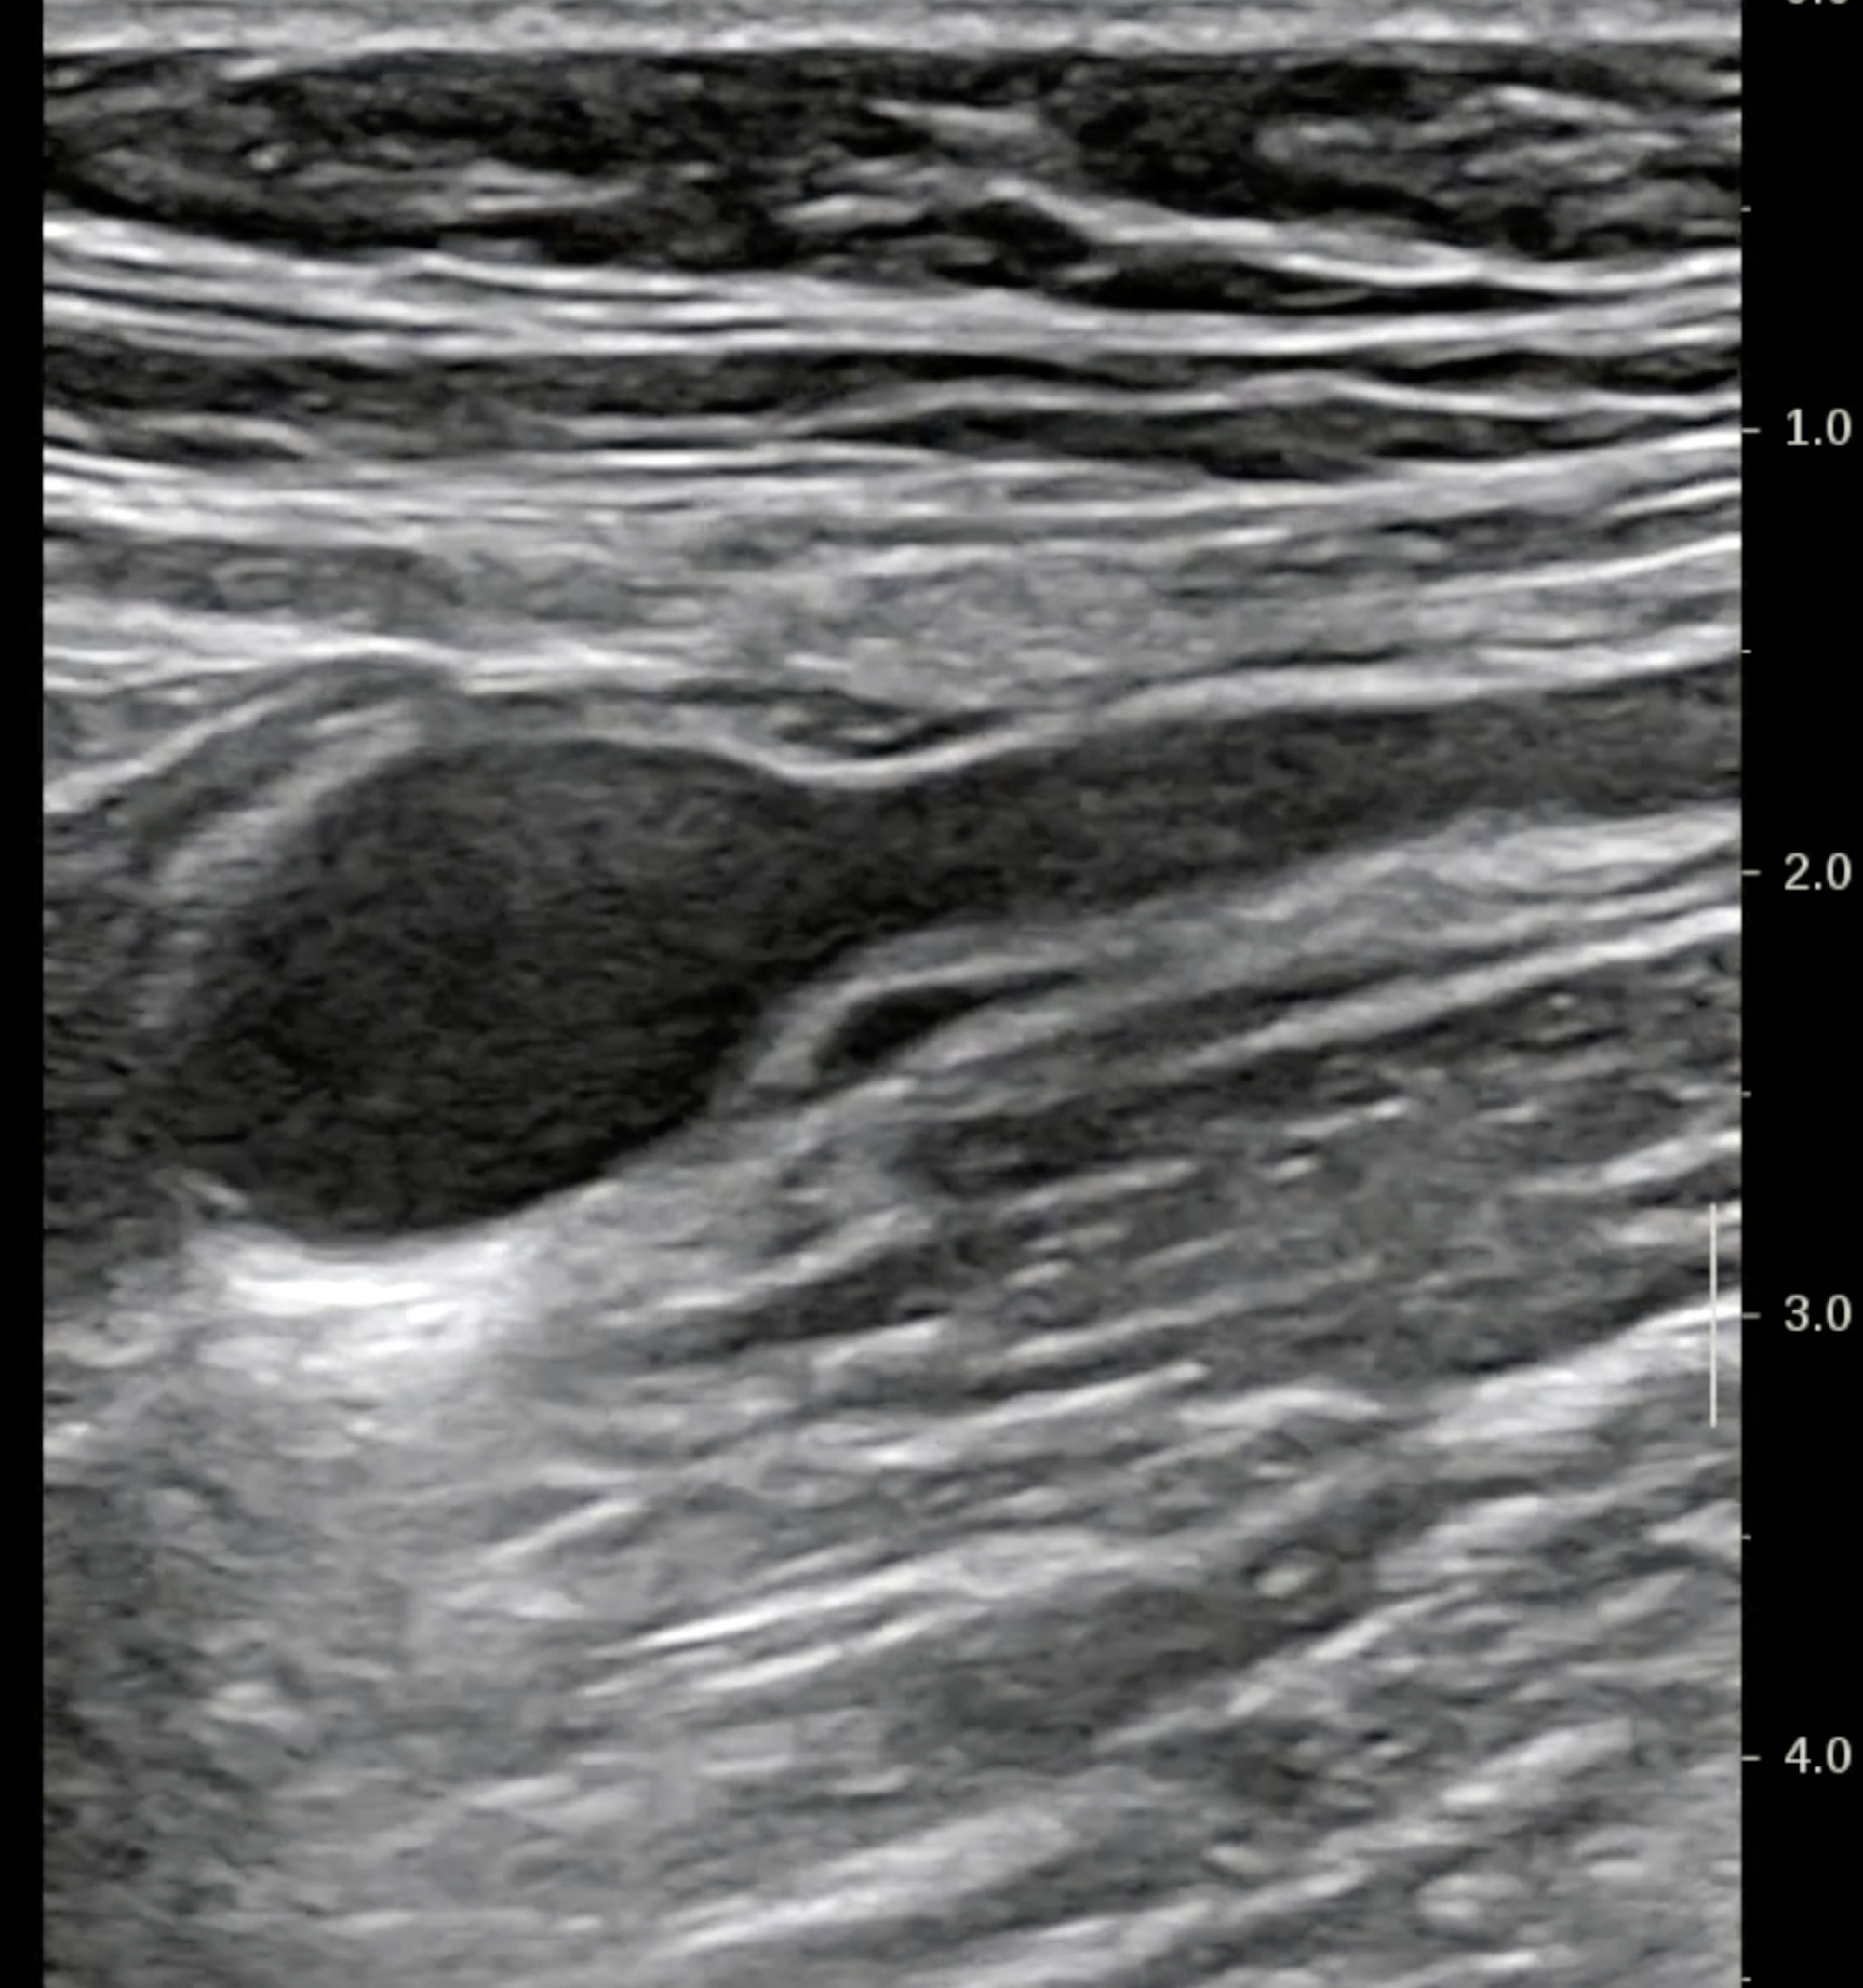

En échographie, à distance (éviter le jour de la coloscopie car l'air peut masquer les images), on voit parfaitement les lésions au delà de l'orifice appendiculaire, la tumeur fait 18 mm x 10 mm et l'appendice au delà est rempli de mucus.

Pointe de l'appendice distendue (7.5 mm de large)